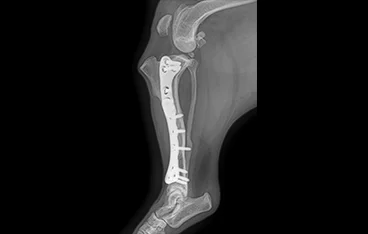

골절

골절 수복(screw, plate, k-wire, pin 등)

• PLATE

• PLATE 수술 전

PLATE 수술 후

• 복합골절

• 최소침습 골절수술